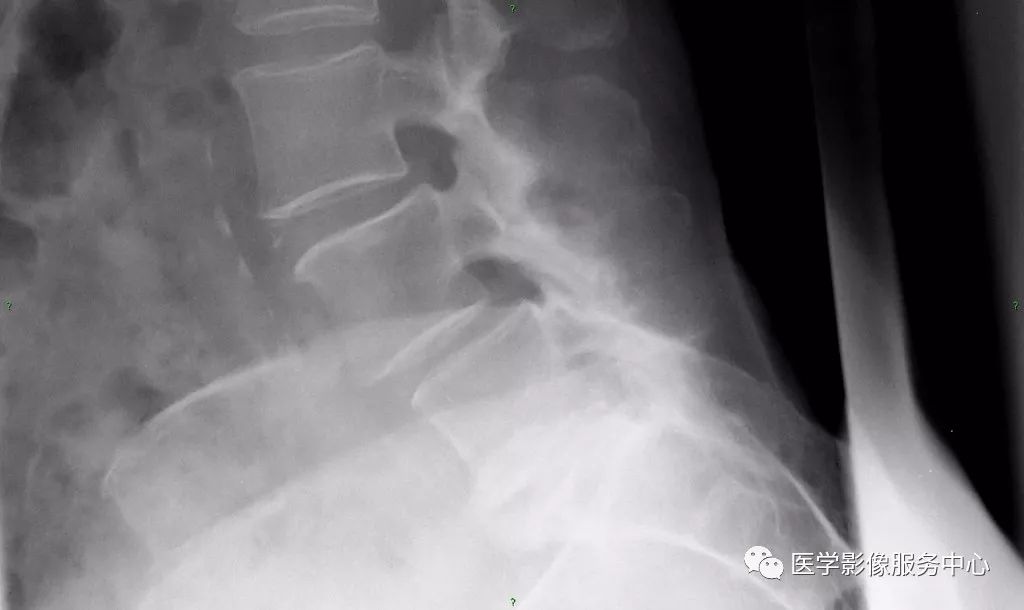

巴斯特鲁普 (氏) 病患者腰椎邻近的棘突相互靠近、撞击致相对缘骨质增生、硬化,棘突呈杵状增粗(反应性肥大),并列的棘突间表面变平及反应性硬化,甚至形成假关节。单节段棘突受累者少见,更多为多节段棘突受累。

X线、CT表现为棘突相对缘骨质增生,密度增高、肥厚,甚至形成假关节及棘突间积气。